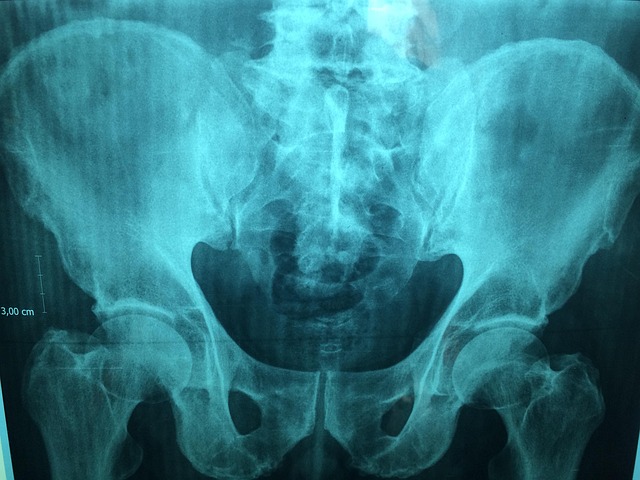

Alkaptonuria arthropathy is a joint condition that develops in individuals with Alkaptonuria, a rare metabolic disorder. In this condition, excess homogentisic acid accumulates and deposits in joint c...